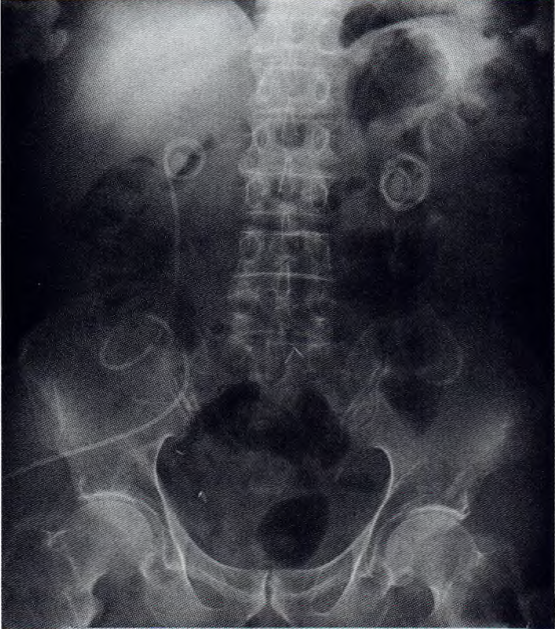

根治术后4年,发现左输尿管腹壁造口单J管回缩3 d入院。入院前1个月KUB检查双侧单J管位置正常。入院后KUB检查示左输尿管腹壁造瘘单J管回缩,大部分蜷缩于肾盂,肾盂结石形成(图1)。

图1患者KuB检查示左侧单J管回缩至肾盂